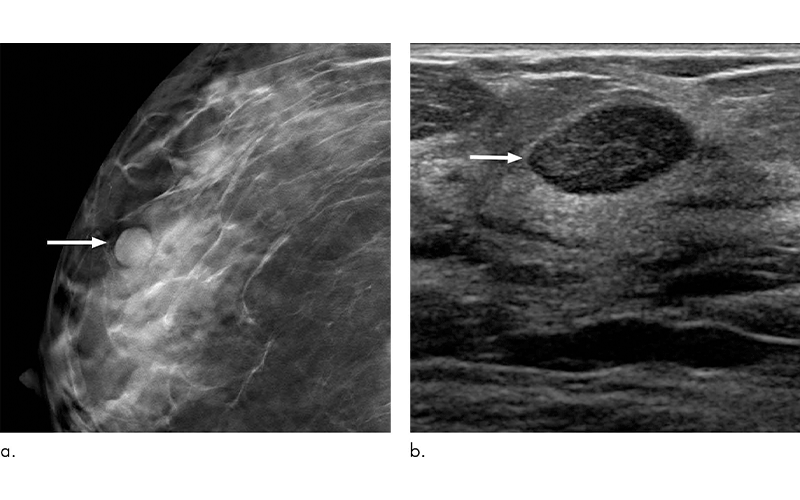

Women with mammographically detected breast lesions that are probably benign should have follow-up surveillance imaging at six months due to the small but not insignificant risk that the lesions are malignant, according to a new study published in the journal Radiology.

The Breast Imaging and Reporting System (BI-RADS) was established by the American College of Radiology to help classify findings on mammography. Findings are classified based on the risk of breast cancer, with a BI-RADS 2 lesion being benign, or not cancerous, and BI-RADS 6 representing a lesion that is biopsy-proven to be malignant.

BI-RADS 3, a probably benign finding, is a particularly challenging category that can cause confusion for physicians and anxiety for patients. This assessment means that the lesion is one of a few specific findings that has been shown to have less than a 2 percent chance of being cancer and that any cancer present is not likely to spread in the time frame recommended for follow-up imaging.